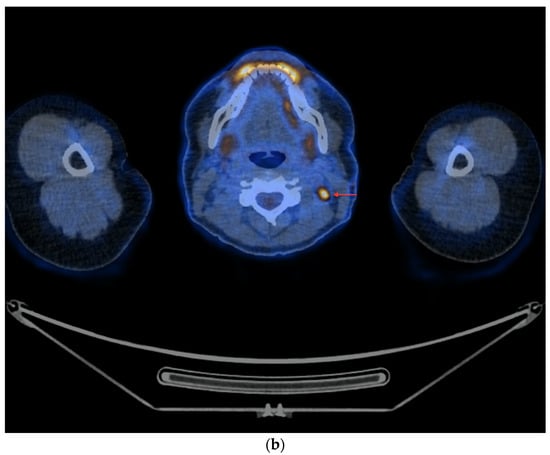

- In the case of potentially resectable lesions, the lesions were operated on after the FNA verification (Figure 3a,b).

Figure 3. PET/CT with [18F]FDG (a) Maximum-intensity projection (MIP). (b) Axial fusion projection. These show an example of the accumulation of the [18F]FDG in the left cervical lymph node (red arrow). The lesion was verified as being metastasized DTC using FNA and resected. The preoperative sTg concentration was 5.55 ng/mL. In the postoperative follow-up, the sTg concentration decreased to being undetectable (<0.04 ng/mL). - -